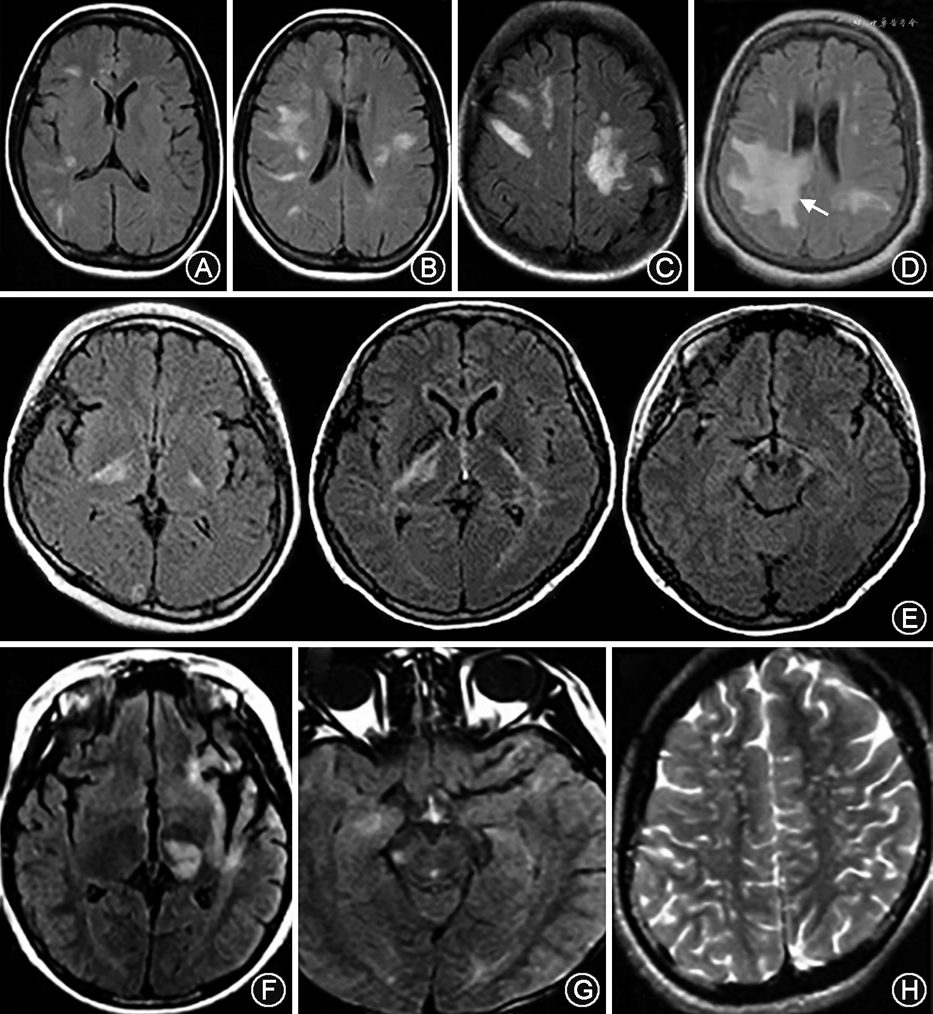

3.最后区综合征:以延髓背侧为主,主要累及最后区域,呈片状或线状长T2信号,可与颈髓病变相连(图3D~F)。

4.急性脑干综合征:可见脑干背盖、四脑室周围弥漫性病变(图4A~C)。

5.急性间脑综合征:位于丘脑、下丘脑、三脑室周围弥漫性病变(图4D、E)。

6.大脑综合征:不符合典型MS的影像学特征,幕上部分病变体积较大,呈弥漫云雾状,无边界,通常不强化,可有散在点状、泼墨状病变。胼胝体病变较弥漫,纵向可大于1/2胼胝体长度。部分病变可沿基底节、内囊后支、大脑脚锥体束走行,T2、FLAIR呈高信号。少数病变可表现类ADEM、肿瘤样脱髓鞘或可逆性后部白质脑病样特征(图5)。